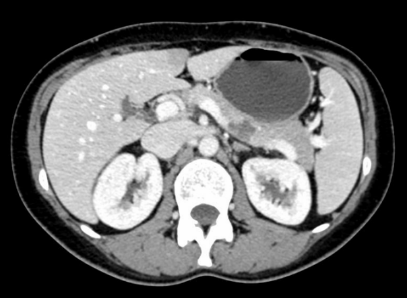

患者36岁,女性,因尿路结石在外院就诊行CT检查,结果提示,胰腺体部见一囊实性结节影,大小约1.4 cm×1.9 cm,边界尚清晰。

增强扫描病灶内见少许强化分隔影,主胰管穿行于肿瘤中但未见扩张。患者辗转多家医院均被告知需行胰腺体尾部切除,甚至可能切除脾脏。如果切除胰腺体尾部,就意味着可能出现新发糖尿病的风险。

图 术前腹部增强CT